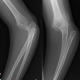

Thorax und Abdomen waren fast ohne Befund, nur die Lunge erlitt Kontusionen. Was aber nicht ungewöhnlich bei einem Hochrasanztrauma ist. Zudem hatte der Patient multiple Frakturen an beiden Beinen.